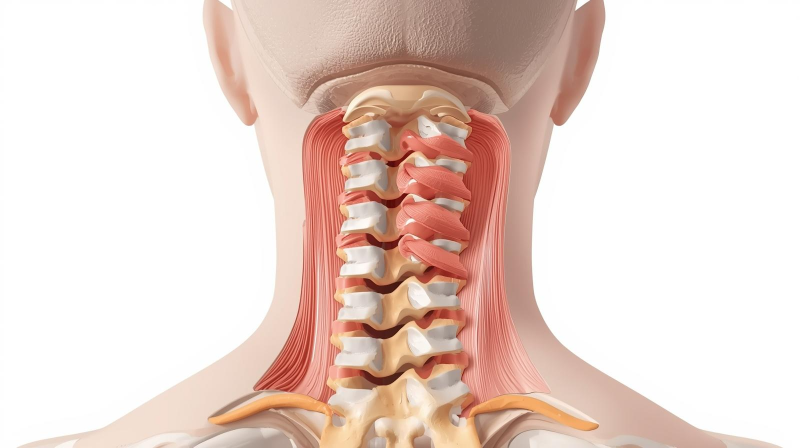

2. 목뼈와 그 변형의 이해

(1) 정상 목뼈

- 측면에서 보았을 때 C자 곡선이 자연스러운 상태

- 충격 흡수 및 균형 유지

(2) 일자목 (Straight Neck)

- C자 곡선이 사라지고 일자로 펴진 상태

- 원인: 잘못된 자세, 장시간 독서·스마트폰 사용

- 증상: 만성적인 목·어깨 통증, 피로, 긴장성 두통

(3) 거북목 (Forward Head Posture)

- 목뼈의 커브 소실 + 머리가 앞으로 빠진 상태

- 어깨가 굽고 등이 구부정해 보임

- 목 각도가 앞으로 기울어질수록, 목 뒤 근육이 지탱해야 할 무게가 급격히 증가